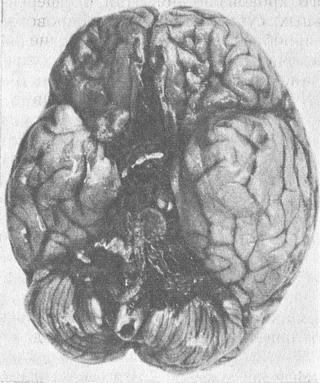

Рис. 17. Базальное субарахноїдальний крововилив.

Особливе місце займають базальні субарахноїдальні крововиливи, які зазвичай є наслідком своєрідного патофизиологического стану організму (хворобливі зміни судин головного мозку, високі артеріальний і внутрішньочерепний тиск та ін). Базальні субарахноїдальні крововиливи (рис. 17) можуть виникати в стані алкогольного сп'яніння, при фізичних напругах, в тому числі і в ситуаціях, пов'язаних з травмою, що значно ускладнює оцінку причинно-наслідкового зв'язку смерті з попередніми подіями. Поряд з цим відомі варіанти виникнення базальних субарахноїдальних крововиливів внаслідок механічних впливів на тіло людини. Так, наприклад, при ударі тупим предметом в область передньобокової частини шиї (звичайно при наявності особливого різновиду анатомічної будови сигмовидного синуса) можливо виникнення базального субарахноїдального крововиливу. При диференціальній діагностиці базальних субарахноїдальних крововиливів велике значення набувають морфологічні та біофізичні методи дослідження головного мозку, що підтверджують (або виключають) його забиття та струс.